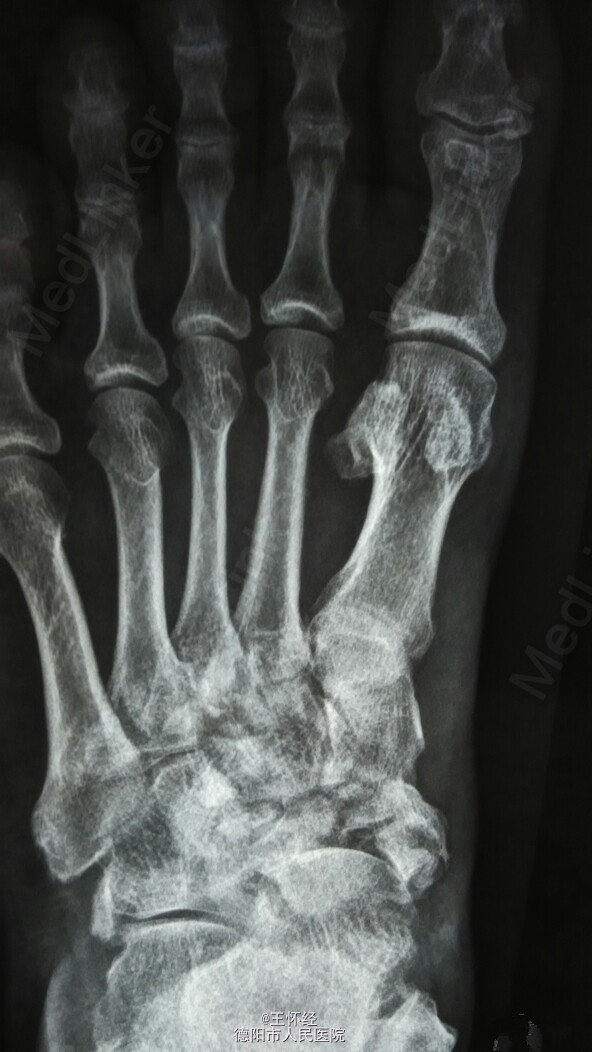

舟骨骨折

患者男性,49岁,外伤后急诊入院,发现舟骨骨骨折,行手术治疗